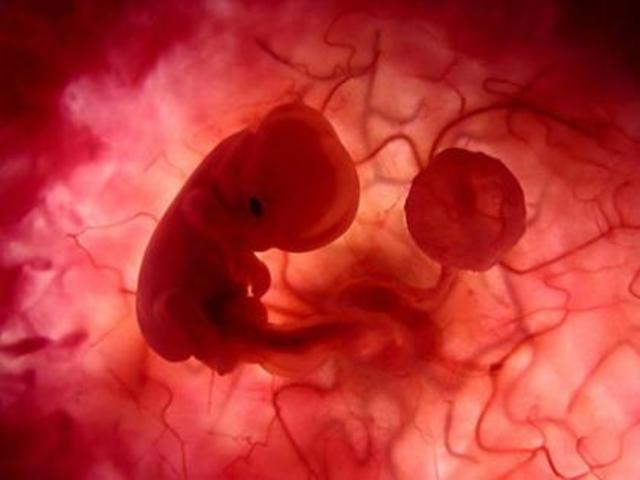

• CIGOTO

CIGOTO

Aparece el embrión producto de la unión de las celulas masculinas y femeninas.

• mórula

mórula

La división célular da como resultado 16 células

• Blastulación

Blastulación

En este estado llega al útero, donde la mórula se va a modificar por la penetración de líquido de la cavidad uterina, que se ubica entre las células formándose una cavidad, llamada blastocele, iniciándose el estado embrionario, en el día 5 posterior a la ovulación.